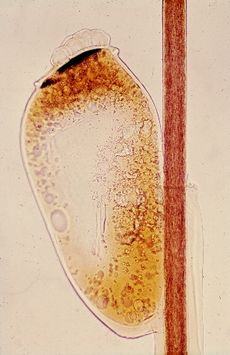

Head louse egg (nit) attached to hair shaft of host

Like most insects, head lice are oviparous. Females lay about three or four eggs per day. Louse eggs or nits, are attached near the base of a host hair shaft.[11][12] Egg-laying behavior is temperature dependent and likely seeks to place the egg in a location that will be conducive to proper embyro development (which is, in turn, temperature dependent). In cool climates, eggs are generally laid within 3–5 mm of the scalp surface.[11][12] In warm climates, and especially the tropics, eggs may be laid 6 بوصات (15 cm) or more down the hair shaft.[13]

To attach an egg, the adult female secretes a glue from her reproductive organ. This glue quickly hardens into a "nit sheath" that covers the hair shaft and large parts of the egg except for the operculum, a cap through which the embryo breathes.[12] The glue was previously thought to be chitin-based, but more recent studies have shown it to be made of proteins similar to hair keratin.[12]

Each egg is oval-shaped and about 0.8 mm in length.[12] They are bright, transparent, and tan to coffee-colored so long as they contain an embryo, but appear white after hatching.[12][13] Head lice hatch typically six to nine days after oviposition.[11][14]

After hatching, the louse nymph leaves behind its egg shell (usually known as a "nit", see below), still attached to the hair shaft. The empty egg shell remains in place until physically removed by abrasion or the host, or until it slowly disintegrates, which may take 6 or more months.[14]